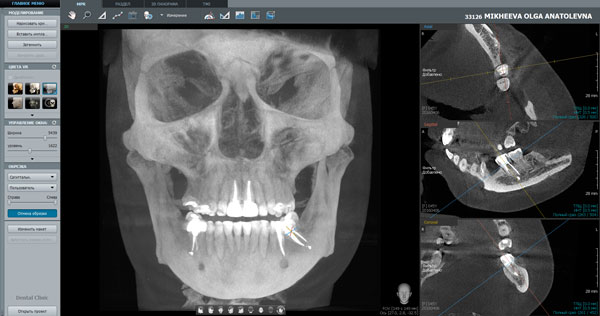

Также в обязанности челюстно-лицевых хирургов зачастую входит проведение костной пластики челюстных костей при атрофии с последующей дентальной имплантацией. Данные 3D –томографии с объемом сканирования 17x15 информируют о состоянии альвеолярных отростков челюстей, зубов, ретромолярных треугольников, при ретенции, дистопии зубов мудрости, ходе нижнечелюстных каналов (Рис.3).

Рис.3 Режим виртуальной реальности в П/О Ez3D-iV4.0 3D-томоргаммы. Аппарат PaX-i3D с объемом сканирования 17x15 от Vatech.